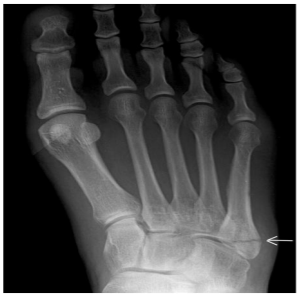

You have broken a bone on the outer part (bottom of the small toe) of your foot. The fracture has occurred in a part of the metatarsal bone which normally heals well without problems.